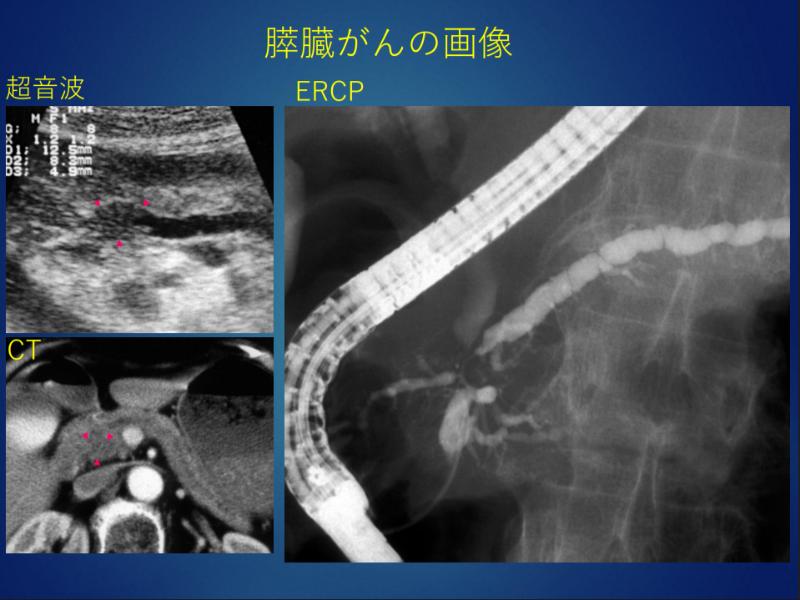

そもそも膵臓がんってどういうものなの?

膵臓内の「膵管」という消化液(膵液)が流れる管から発症するものが一般的で

MRI、CT、超音波内視鏡(EUS)などの精密検査をすることで発見できる病気です。